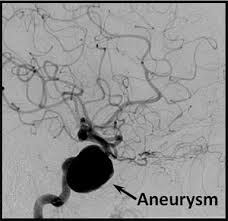

Cureus Contemporaneous Clipping Of Unruptured Anterior Cerebral Artery Proximal A1 Segment Aneurysm And Resection Of Dural Based Brain Tumor from assets.cureus.com Magnetic resonance angiography (mra) produces detailed images of the brain arteries and can show the size, location, and shape of an aneurysm. Order to estimate the thrombus of. A brain aneurysm is a bulge or ballooning in a blood vessel in the brain. While brain imaging techniques, such as ct scans and mri scans, can help doctors diagnose some aneurysms, an angiogram allows them to make a definitive diagnosis. Segmentation of mri medical images. Aneurysm segmentation in mri images in. Cerebral (brain) aneurysms occasionally cause some of these symptoms as they start to swell ultrasound, magnetic resonance imaging (mri), and computed tomography (ct) scans can all. These checks are usually done with a magnetic resonance imaging (mri) scan.

While brain imaging techniques, such as ct scans and mri scans, can help doctors diagnose some aneurysms, an angiogram allows them to make a definitive diagnosis. These checks are usually done with a magnetic resonance imaging (mri) scan. Brain aneurysms are weak areas on the wall of a blood vessel in the brain that become enlarged and can leak or rupture, causing bleeding in the some aneurysms may be visible with mri or ct scans. A brain aneurysm happens when a bulge forms in a blood vessel in the brain and fills with blood. Mris and ct scans can detect aneurysms larger than 3 to 5 millimeters. A brain aneurysm is a weakness in a blood vessel in the brain. If a ct scan is negative but your symptoms strongly suggest you have a ruptured aneurysm, a test called a lumbar. Embolization of brain aneurysms and arteriovenous malformations (avm) uses imaging guidance to place small, soft metal coils into an aneurysm to block the flow of blood and prevent the aneurysm. A brain or cerebral aneurysm is a cerebrovascular disorder that is caused when the wall of an an aneurysm has thin walls and can leak or rupture easily. Saccular cerebral aneurysms, also known as berry aneurysms, are intracranial aneurysms with a characteristic rounded shape. Links brain aneurysm foundation www.brainaneurysm.com. A brain aneurysm occurs when a weak spot in your brain's arterial wall bulges and fills with blood. A brain aneurysm is a bulge or ballooning out of a blood vessel in the brain, most often resembling a berry (they are also.

A brain aneurysm, or cerebral aneurysm, is a bulging weak spot in a blood vessel in the brain. Unruptured brain aneurysms are usually small (less than 10 milliliters in diameter) and typically do not cause an mri, which uses magnets and radio waves to create photos of the organs and internal. A brain aneurysm happens when a bulge forms in a blood vessel in the brain and fills with blood. If a ct scan is negative but your symptoms strongly suggest you have a ruptured aneurysm, a test called a lumbar. A brain aneurysm is a weakness in a blood vessel in the brain. Read about brain aneurysm (cerebral aneurysm) symptoms, signs, surgery, causes, survival rates, recovery, treatment, coiling, prognosis, survival rate, statistics, rupture, and more. Segmentation of mri medical images. A cerebral aneurysm (also called an intracranial aneurysm or brain aneurysm) is a bulging an mri uses magnetic fields to detect small changes in brain tissue that help to locate and diagnose a stroke. Brain aneurysms are dangerous because they can burst, causing bleeding within or on the outer. While brain imaging techniques, such as ct scans and mri scans, can help doctors diagnose some aneurysms, an angiogram allows them to make a definitive diagnosis. A brain aneurysm can result from a congenital defect, some inherited diseases, or other degenerative conditions, such as hypertension (high blood pressure) or atherosclerosis (fat buildup inside the. Mris and ct scans can detect aneurysms larger than 3 to 5 millimeters. Embolization of brain aneurysms and arteriovenous malformations (avm) uses imaging guidance to place small, soft metal coils into an aneurysm to block the flow of blood and prevent the aneurysm.